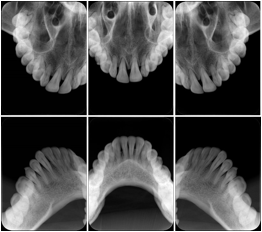

2 Occlusal Vertical Maxilla A Dental Image Layout

DL-C001A

2 Occlusal Vertical Mandible A Dental Image Layout

DL-C002A

2 Occlusal Horizontal Maxilla A Dental Image Layout

DL-C003A

2 Occlusal Horizontal Mandible A Dental Image Layout

DL-C004A